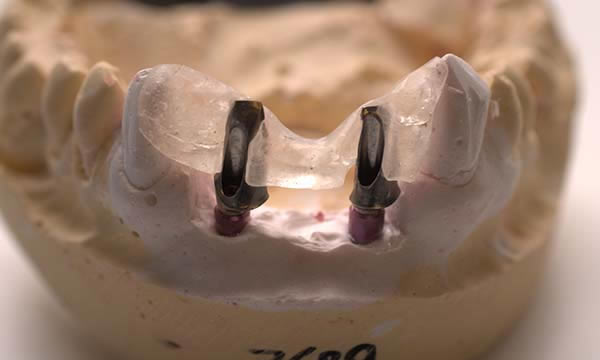

A case of a patient who was a long term resin retained bridge wearer. The resin retained bridge was placed after the patient lost his UL1 many years ago. There was a history of the resin retained bridge lute failing, and due to the loss of the UL1 there was a labio - palatal bone deficit.

A clear acrylic position guide was used to guide implant placement within the aesthetic envelope and guided bone regeneration was used labially to elevate the long standing concavity. A Bonded crown was used to restore the implant and at the 12 month follow up, the bone level around the implant remains unchanged and the patient is confidently smiling.

Case C

During Treatment